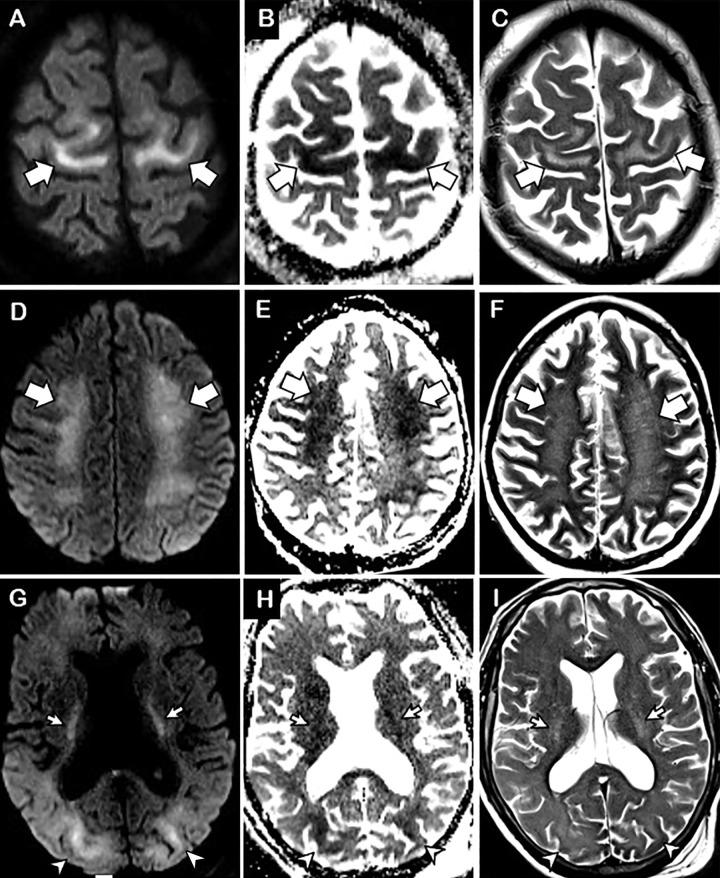

COVID-19-associated Diffuse Leukoencephalopathy and Microhemorrhages.

Diffuse leukoencephalopathy and juxtacortical and/or callosal microhemorrhages were brain imaging features in critically ill patients with coronavirus disease 2019. Coronavirus disease 2019 (COVID-19) has been reported in association with a variety of brain imaging findings such as ischemic infarct, hemorrhage, and acute hemorrhagic necrotizing encephalopathy. Herein, the authors report brain imaging features in 11 critically ill patients with COVID-19 with persistently diminished mental status who underwent MRI between April 5 and April 25, 2020. These imaging features include confluent T2 hyperintensity and mild restricted diffusion in bilateral supratentorial deep and subcortical white matter (in 10 of 11 patients) and multiple punctate microhemorrhages in juxtacortical and callosal white matter (in seven of 11 patients). The authors also discuss potential pathogeneses.